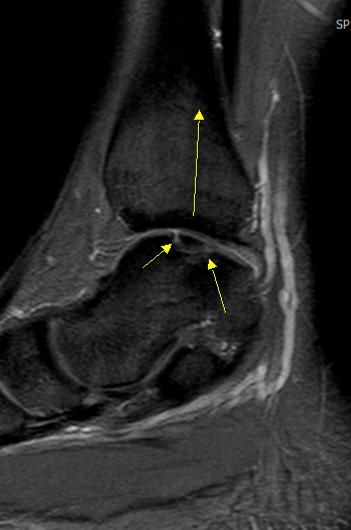

골연골염이 체중 부하 관절면에 몇퍼센트 정도 되어있는건지 판독 부탁드립니다

• 3번 째 사진